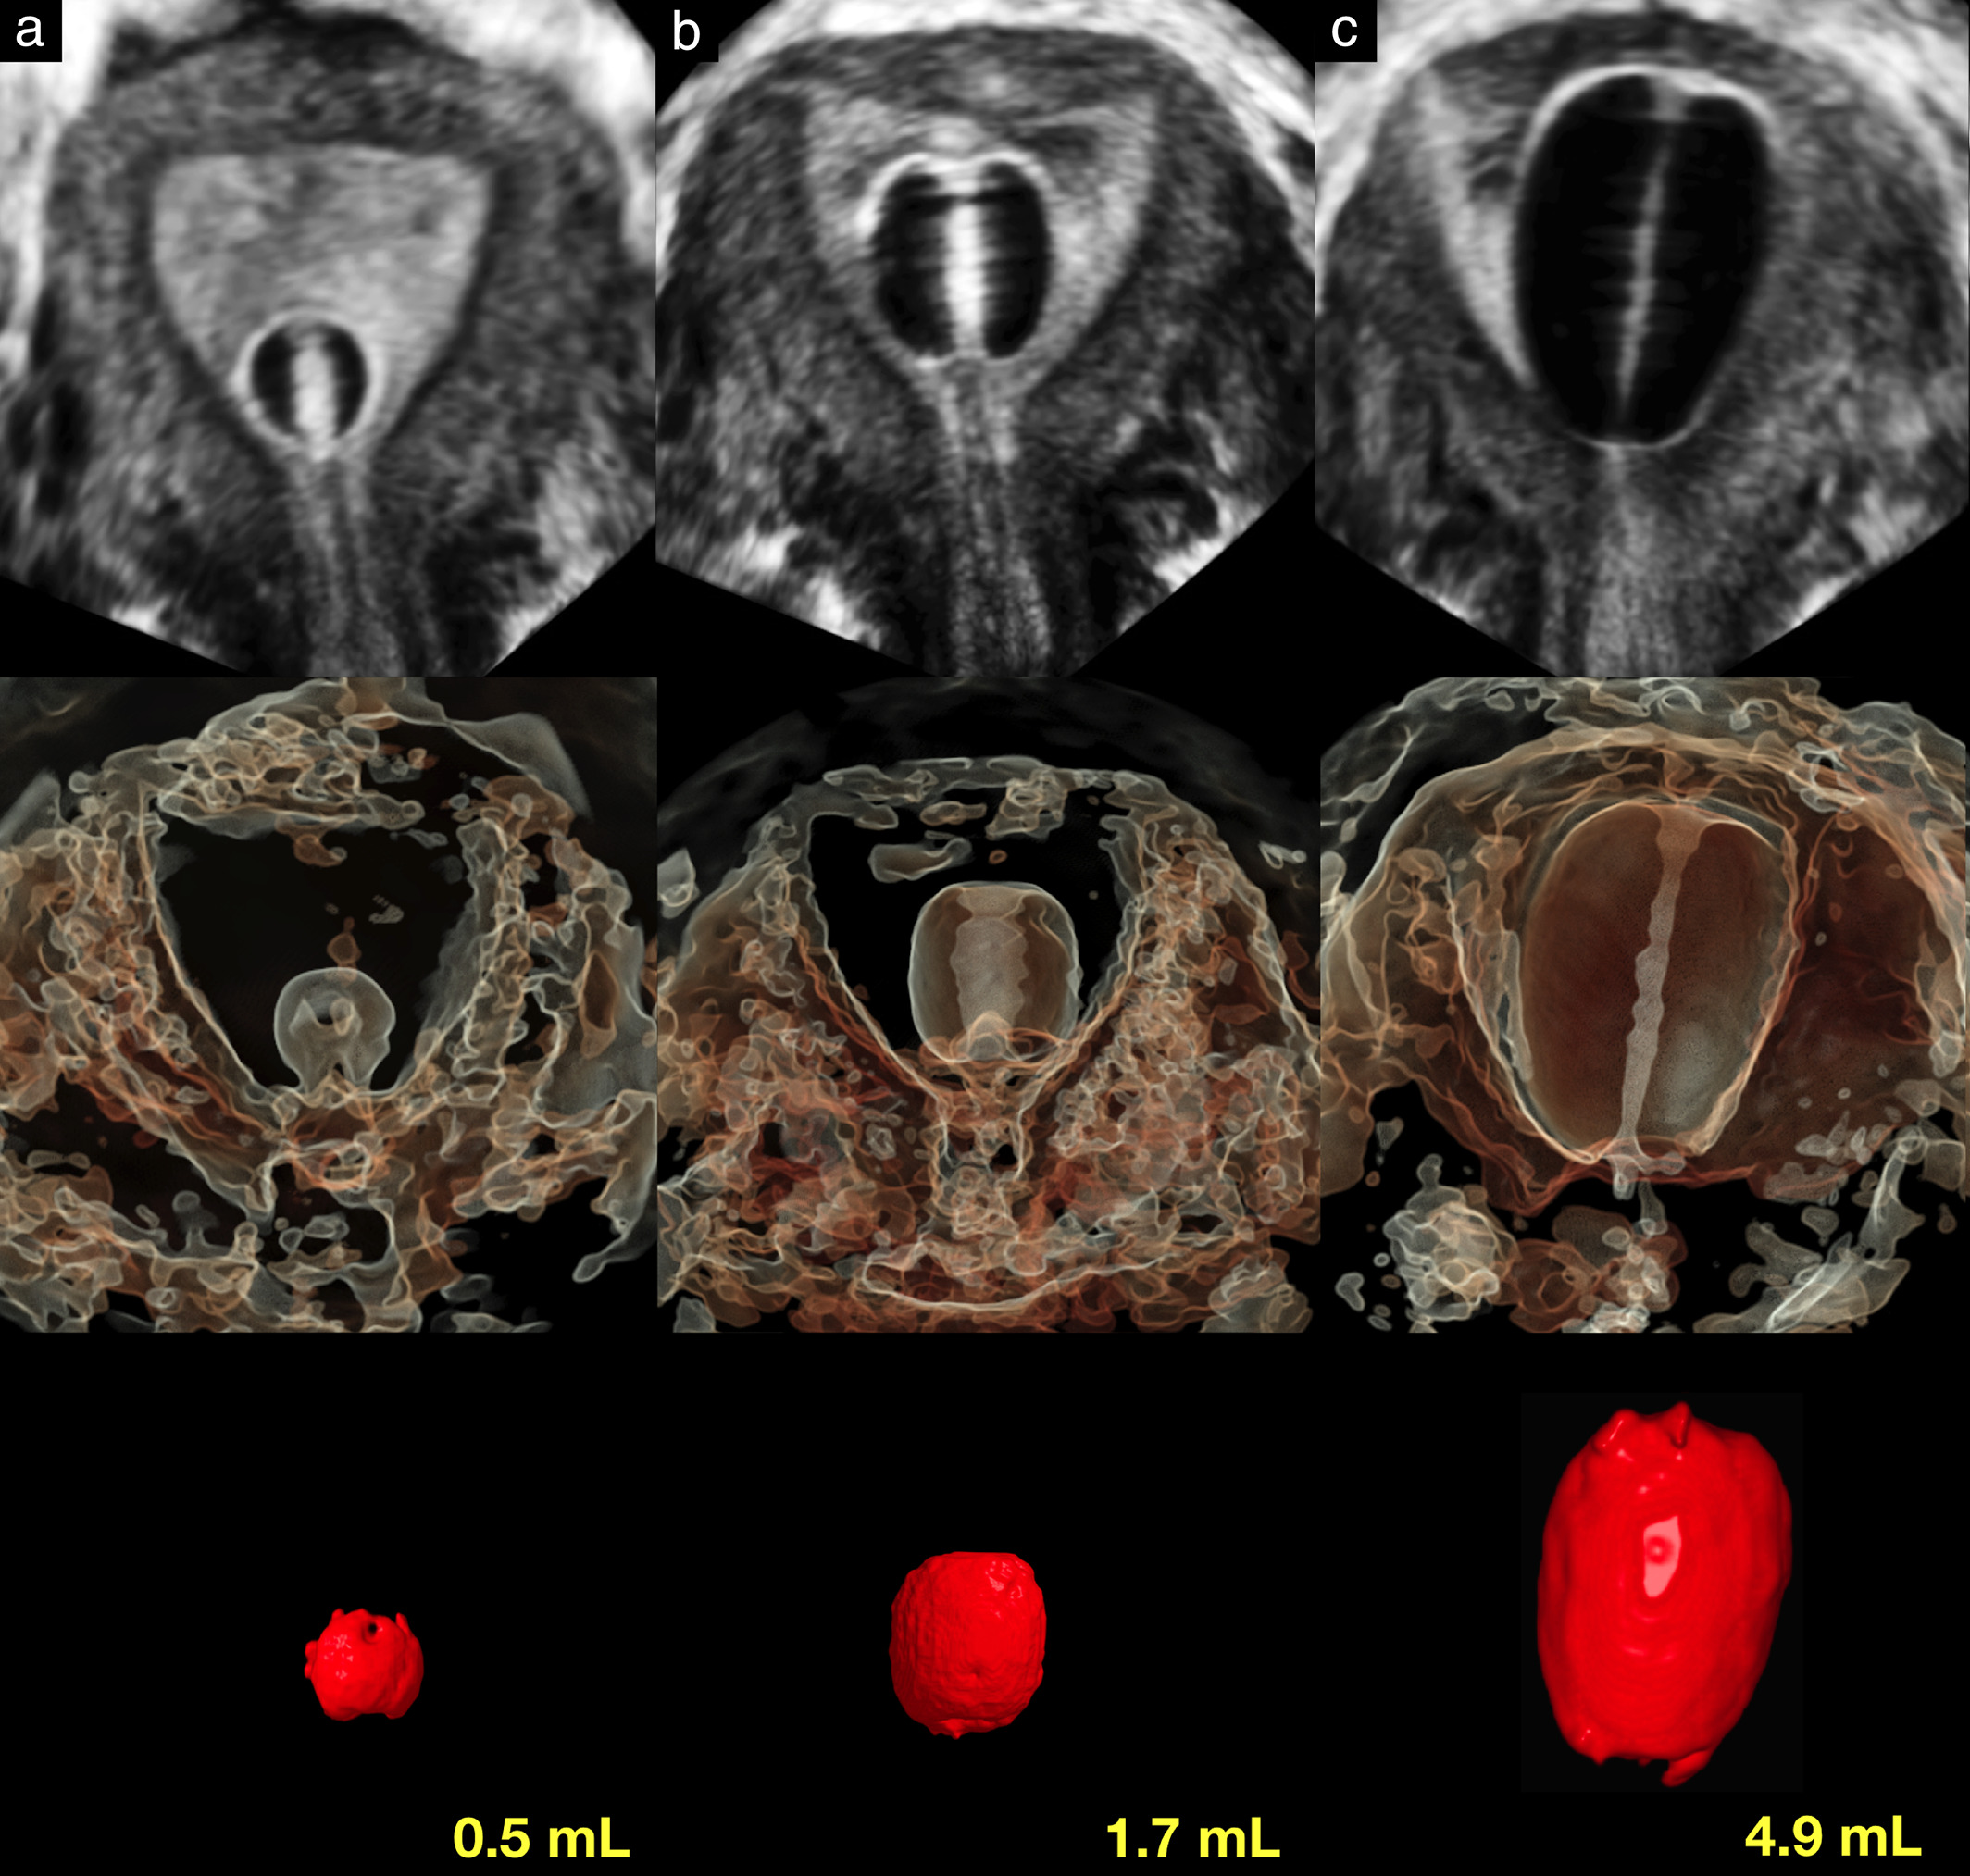

Uterine cavity imaging, volume estimation and quantification of degree of deformity using automatic volume calculation: description of technique

Więcej